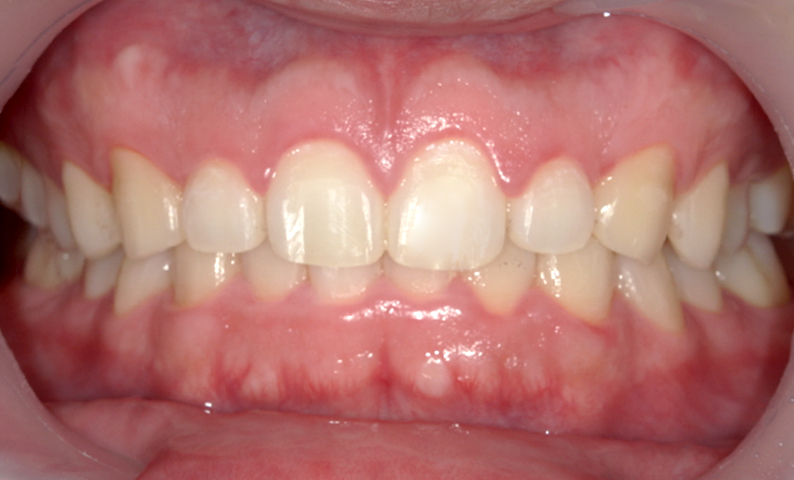

| 治療前 | 治療後 |

|---|---|

|